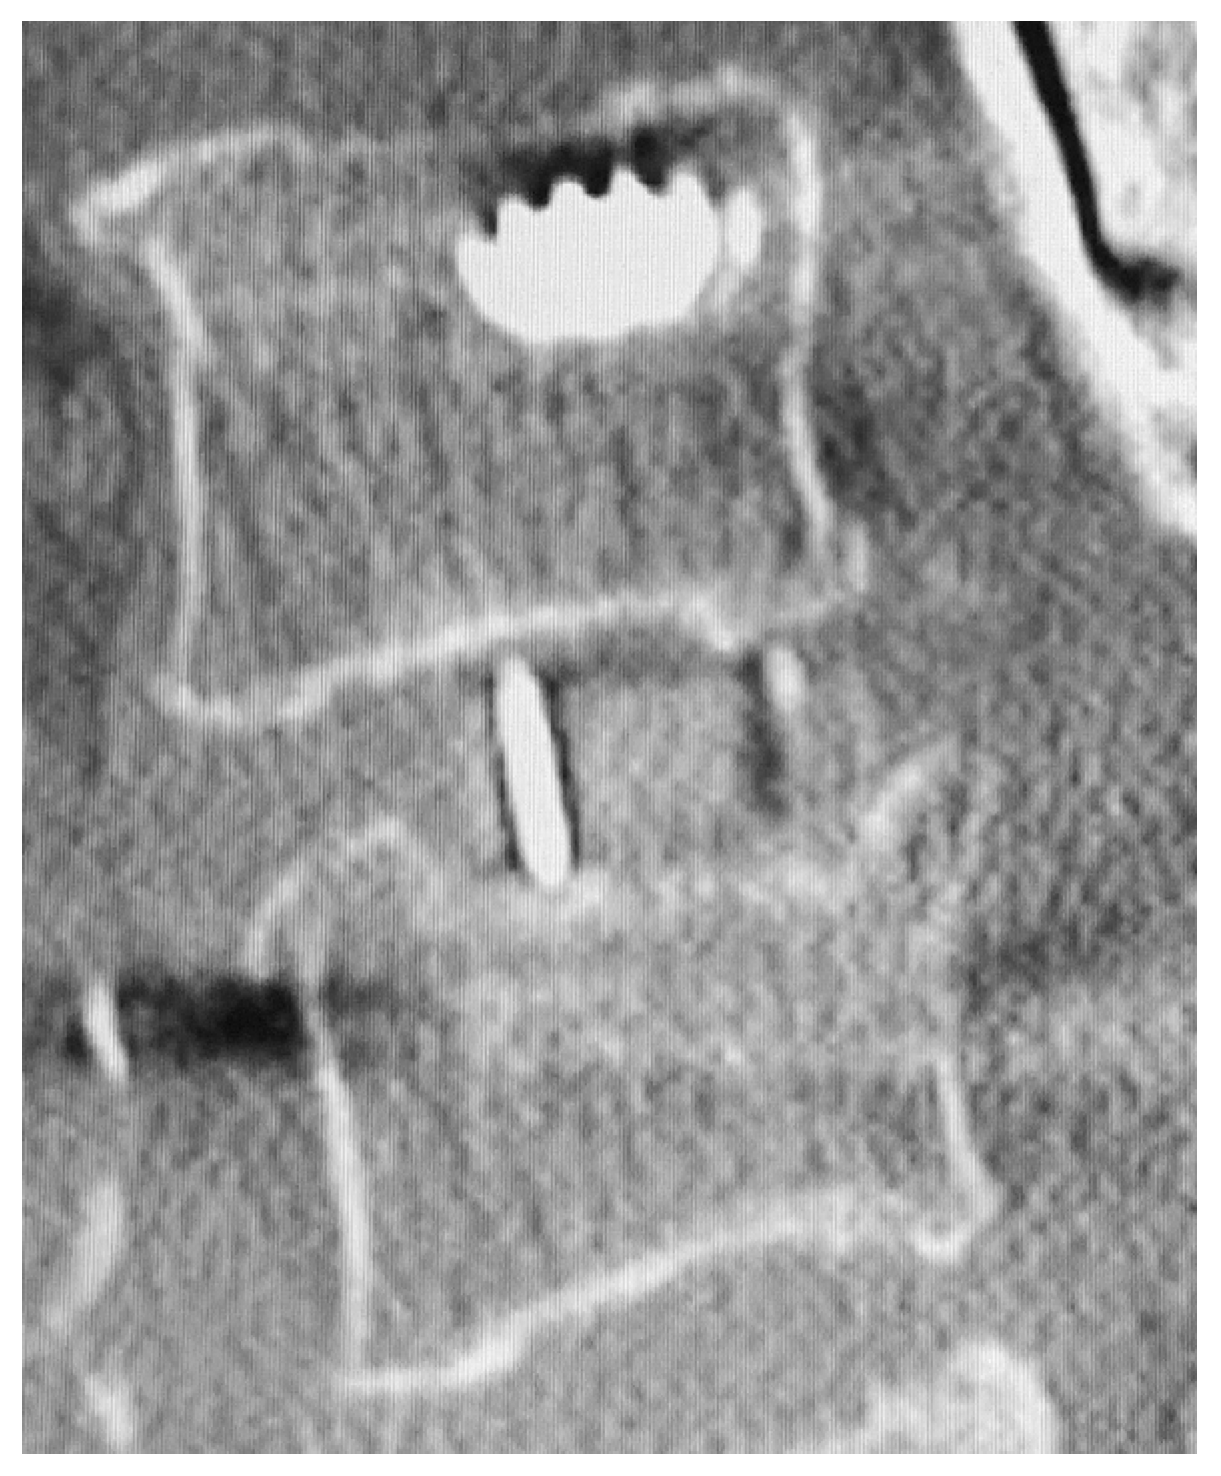

2.3. Radiological Assessment

- Malham, G.M.; Parker, R.M.; Blecher, C.M.; Seex, K.A. Assessment and classification of subsidence after lateral interbody fusion using serial computed tomography. J. Neurosurg. Spine 2015, 23, 589–597. [Google Scholar] [CrossRef] [PubMed] [Green Version]

- Marchi, L.; Abdala, N.; Oliveira, L.; Amaral, R.; Coutinho, E.; Pimenta, L. Radiographic and clinical evaluation of cage subsidence after stand-alone lateral interbody fusion. J. Neurosurg. Spine 2013, 19, 110–118. [Google Scholar] [CrossRef]

| Early Cage Subsidence (ECS) | 9/59 (15.3) | |

| Delayed Cage Subsidence (DCS) | 11/59 (18.6) | |

| Cage Subsidence | 20/59 (33.9) | |

| By location | Unilateral endplate | 16 (80.0) |

| Bilateral endplate | 4 (20.0) | |

| Endplate cranial to disc | 9 (37.5) | |

| Endplate caudal to disc | 15 (62.5) | |

| Marchi Classification | Grade 1 | 11 (55.0) |

| Grade 2 | 5 (25.0) | |

| Grade 3 | 4 (20.0) | |